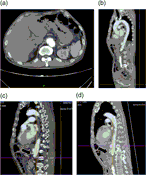

Immediate successful renal autotransplantation after proximal ureteral avulsion fallowing ureteroscopy: a case report

Mansor Alizadeh and others

Journal of Surgical Case Reports, Volume 2017, Issue 2, February 2017, rjx028, https://doi.org/10.1093/jscr/rjx028